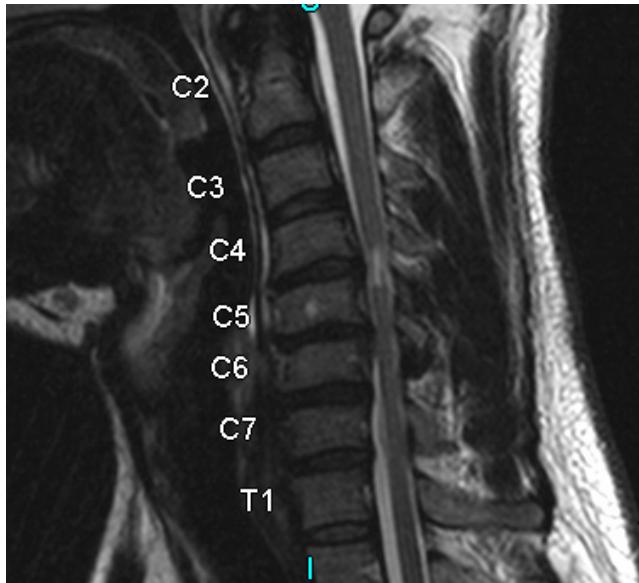

Imaging:

- MRI: Study of choice to evaluate degree of spinal cord and nerve root compression

Imaging Examples:

Surgical Treatment - Anterior Cervical Discectomy and Fusion: